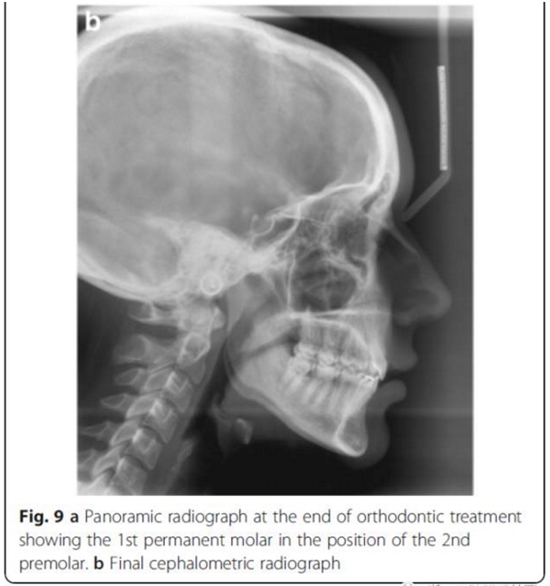

頭側(cè)分析,骨性I類(lèi)關(guān)系,高角型

雙側(cè)I類(lèi)尖牙和磨牙關(guān)系;完全的間隙關(guān)閉(用牙線(xiàn)確定);覆合覆蓋糾正;仍有輕度的中線(xiàn)偏離。頭測(cè)分析顯示,下切牙未發(fā)生舌側(cè)移動(dòng)。